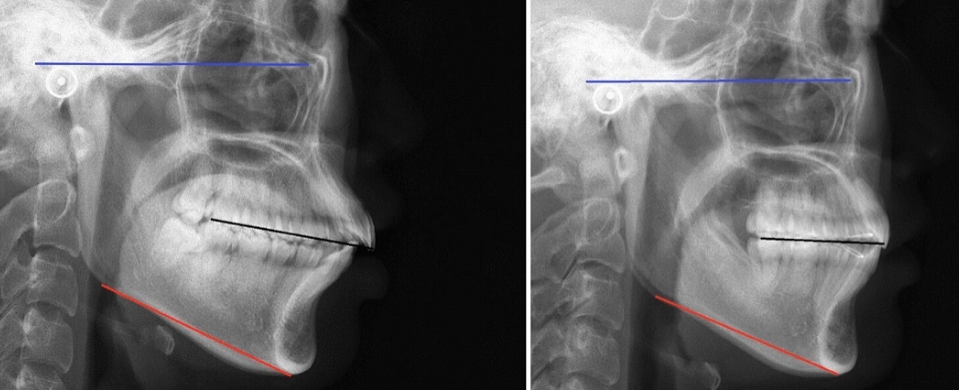

一下x光片,见证奇迹的时刻,下颌发生的逆时针旋转,让你的下巴"长"出来

开唇露齿 下巴后缩 | 隐适美骨性前突案例